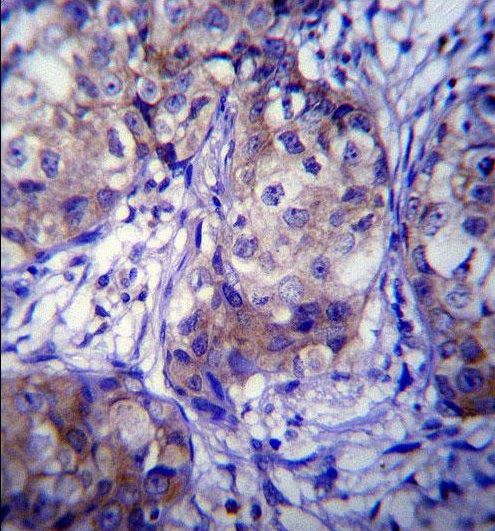

IHC-P analysis of human breast carcinoma using GTX81231 CYP1A1 antibody, Internal.